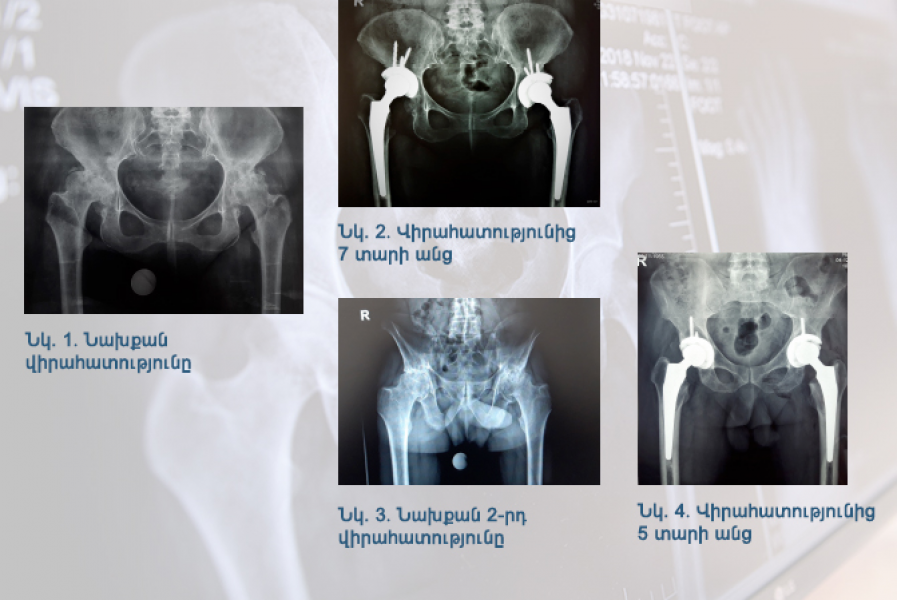

Клинический случай: двусторонний анкилозирующий коксартроз

В медицинский центр «Наири» обратился мужчина 1951 года рождения с двусторонним анкилозирующим коксартрозом и ожирением первой степени․․․

12 Апрель 2022 | Ортопедия и травматология, "Кокса" клиника | Грачья Геворкович Арутюнян